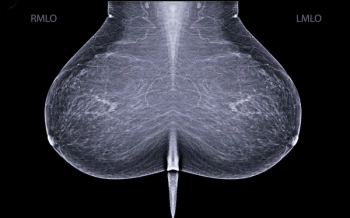

In multiple mammography datasets with the original radiologist-detected abnormality removed, deep learning detection of breast cancer had an average area under the curve (AUC) of 87 percent and an accuracy rate of 83 percent, according to research presented at the recent Society for Imaging Informatics in Medicine (SIIM) conference.